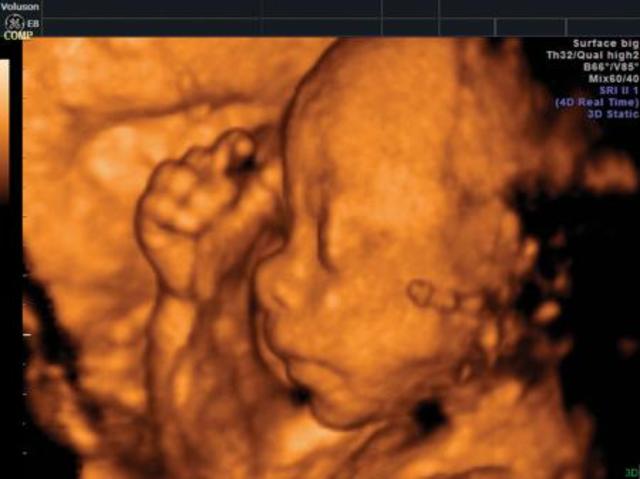

• "SÓLO CARAS BONITAS??"

"SÓLO CARAS BONITAS??"

El exámen sonográfico periódico es muy importante, y la ecografía 3D es una herramienta muy útil, pero no debe emplearse sólo para obtener fotos "hermosas" de la cara del bebé...

• NO SIEMPRE "MÁS ES MEJOR"...

NO SIEMPRE "MÁS ES MEJOR"...

La tecnología debe utilizarse para beneficio del feto y la madre, no sólo para vender más...